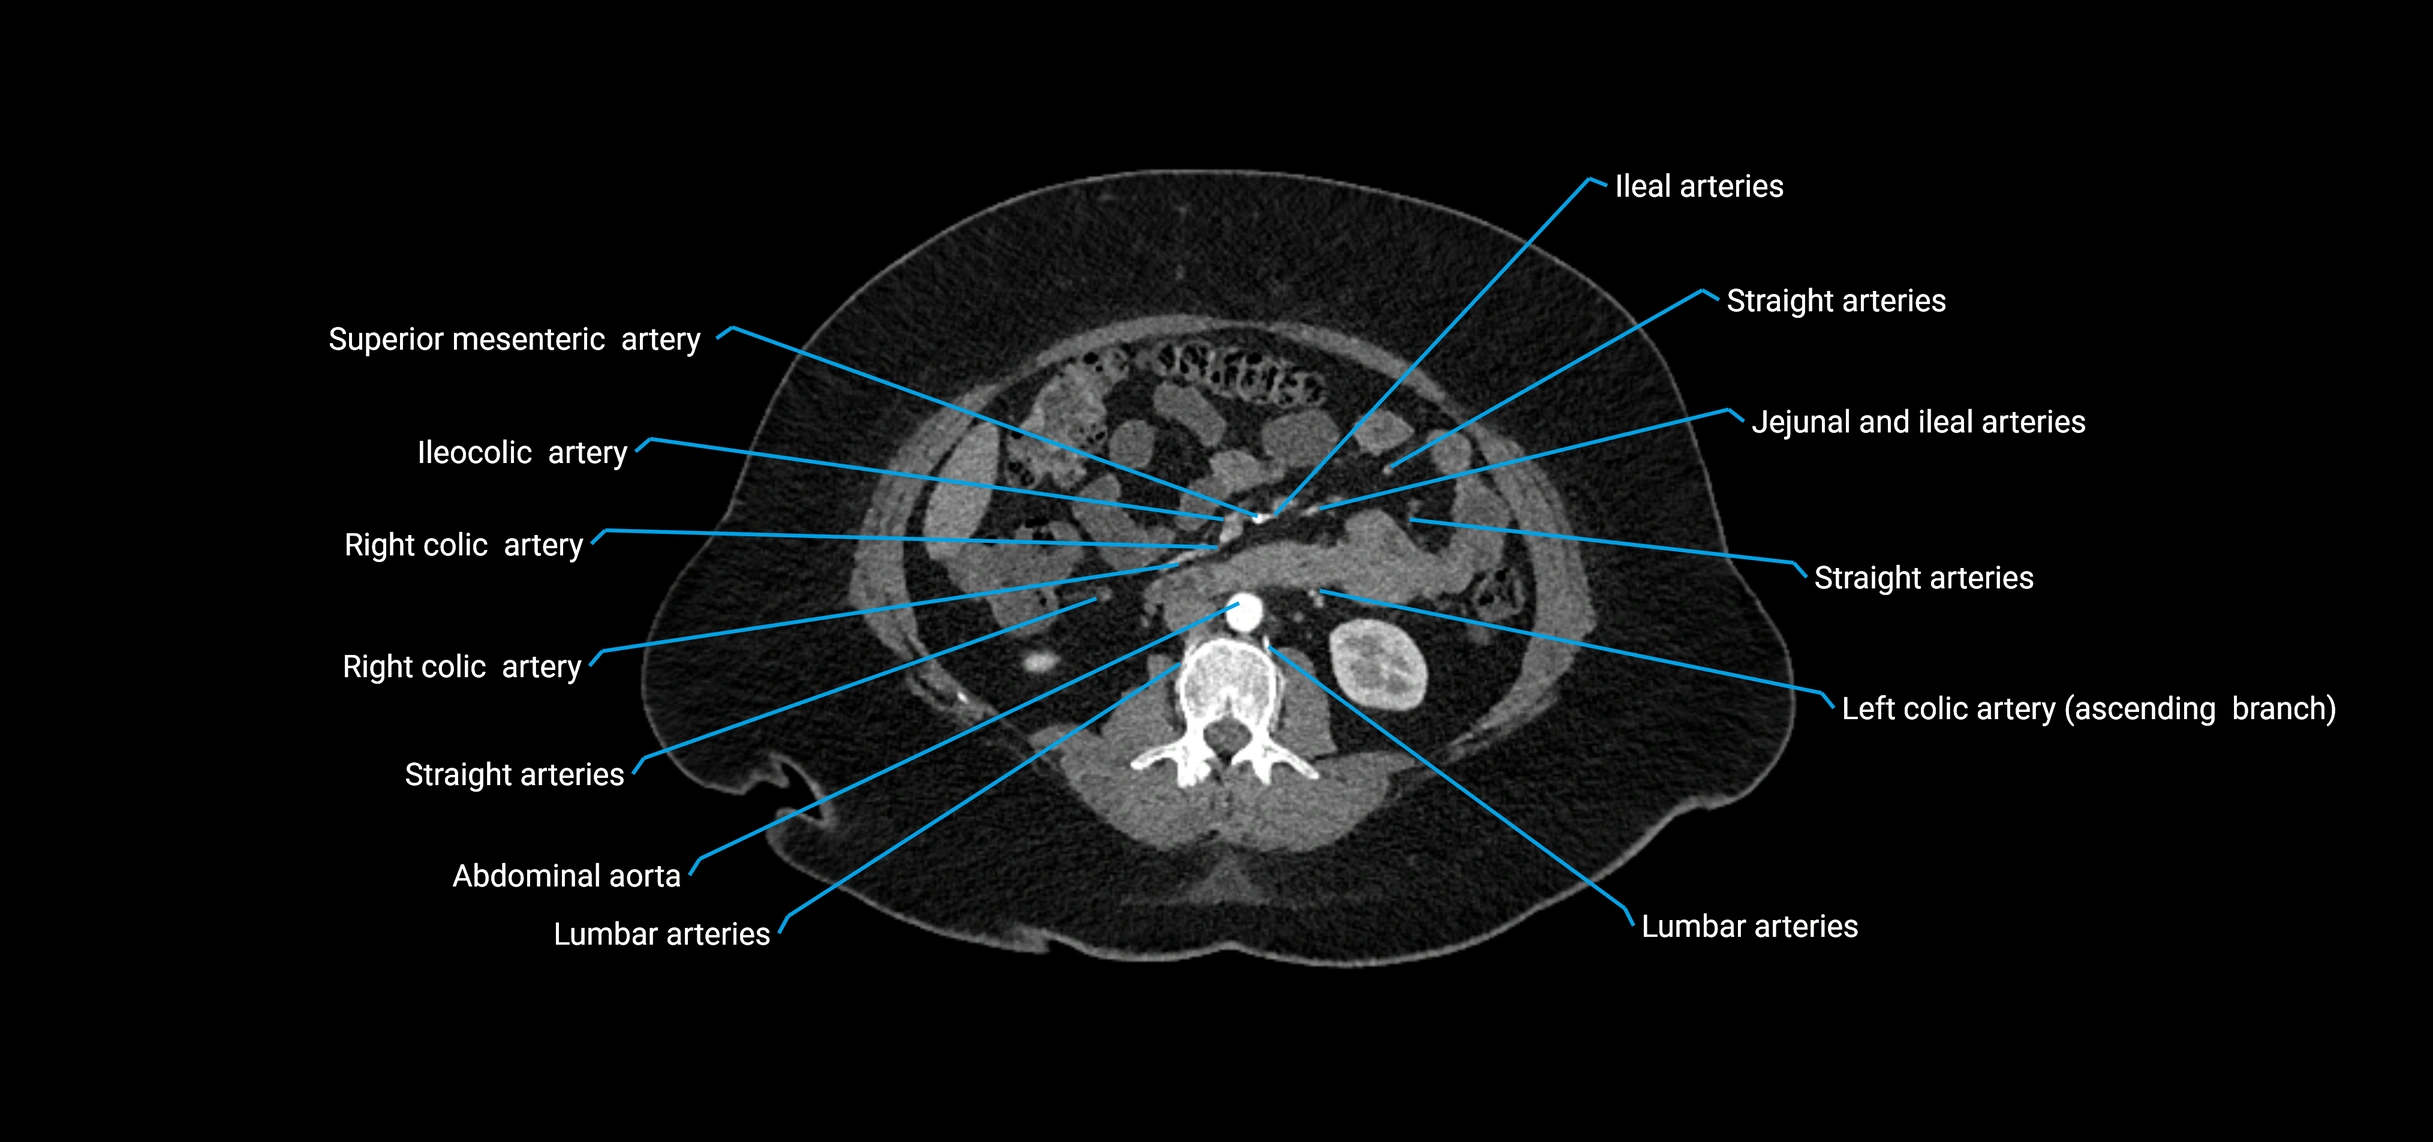

Contrast-enhanced CT (CTA):

• Gold standard for abdominal aortic imaging

• Provides excellent detail of lumen, wall, aneurysm, thrombus, and branch vessels

• Multiplanar and 3D reconstructions help in aneurysm measurement, stent graft planning, and dissection evaluation